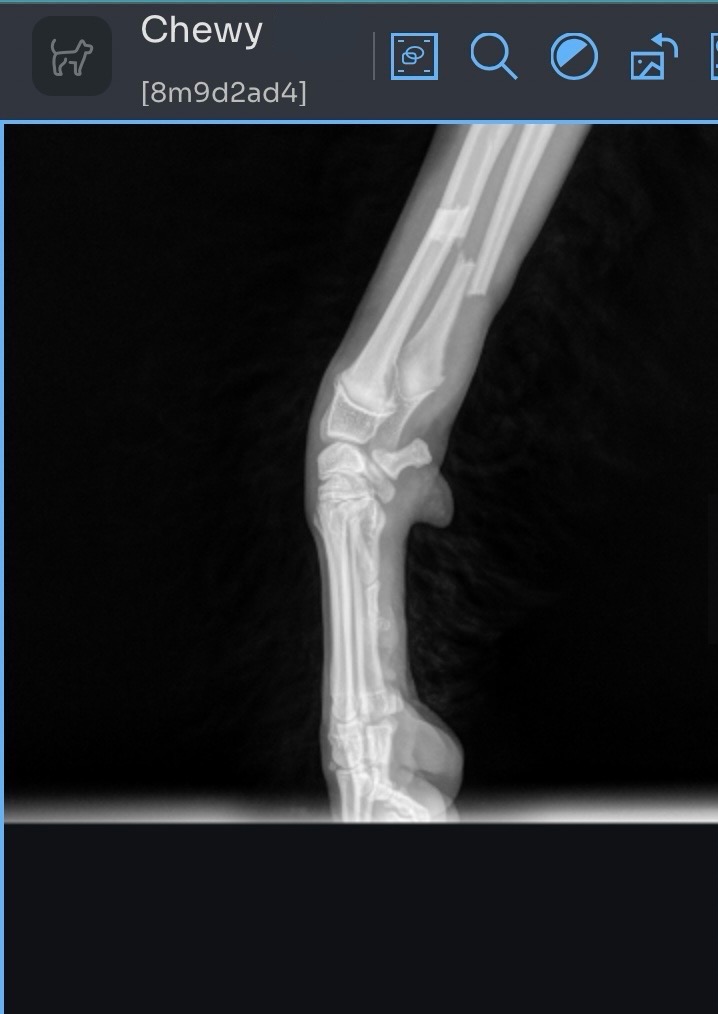

Chewy, my 7 month old puppy, broke two bones in his leg while playing at home over the weekend. After rushing to a late night ER Vet Visit, he is now having emergency surgery on 06/12/25 to have a titanium plate & up to 8 screws put in. His expected recovery is 12 weeks, requiring medicine, rest, and weekly vet visits for a fresh cast/splint.